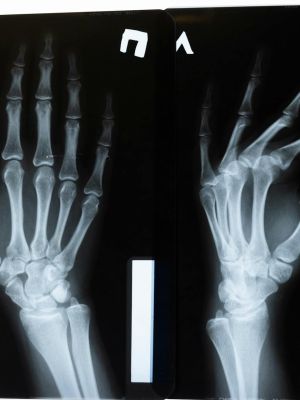

Multislajsni CT pregled zglobova omogućava detaljan prikaz zglobnih struktura i okolnih tkiva, uključujući kosti, hrskavicu, tetive, ligamente, mišiće i krvne sudove. Ova dijagnostička metoda koristi rendgenske zrake i naprednu računalnu obradu kako bi se dobile precizne presečne slike, koje se po potrebi mogu prikazati i u trodimenzionalnom obliku.

Multislajsni CT omogućava veoma precizno sagledavanje struktura zgloba, uključujući i sitne promene koje drugim metodama mogu ostati neprimećene. Po potrebi se koristi kontrastno sredstvo radi boljeg prikaza krvnih sudova i mekih tkiva.

• traumatske povrede i sitne frakture